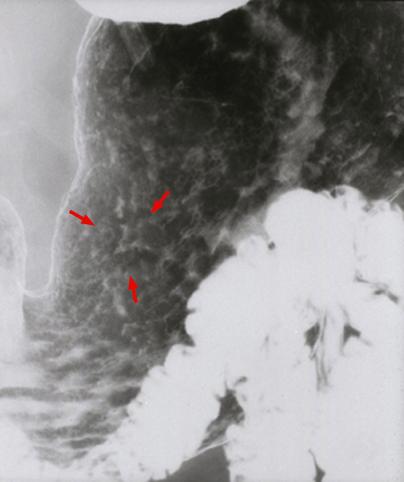

질환(병리주체)의 분류 악성 상피성종양/선암

부위(장기별) 위(부위)/체부

검사방법 X-P

종양의 육안분류 0형(표재형)/IIc형(IIc)

종양의 최대경(밀리미터) 10~14

종양의 심달도 m